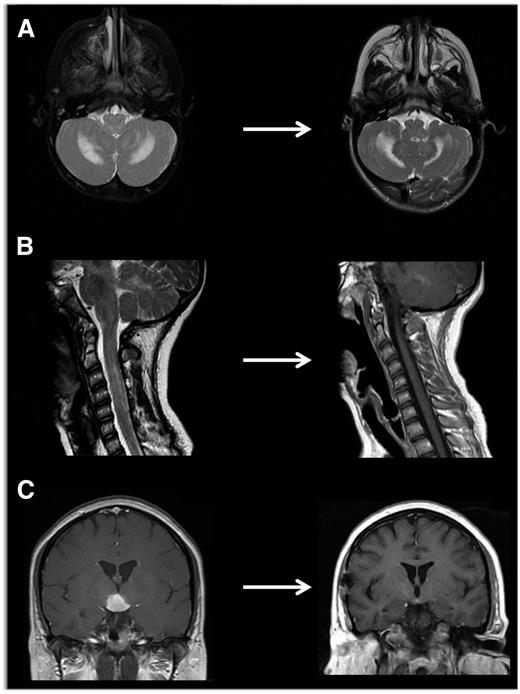

PET scan is effective in evaluating response to treatment of most lesions (Figure 4) except vertebral lesions, which may be better visualized by MRI that will capture changes in soft tissue or enhancement of the bone.28 Vertebral CT scans may add information on bone response to therapy and CT scans are also optimal for following bony lesions of the skull, whereas MRI is most effective for parenchymal brain and pituitary lesions. Bone healing may lag resolution of other lesions (Figures 5-6). CT scanning is also an optimal study to evaluate lung lesions, though cysts may remain as permanent consequences following resolution of nodular parenchymal lung lesions (Figure 7). Clinical examination is sufficient follow-up for proven skin-limited disease, and patients with single bone lesions may be followed by clinical examination, radiograph, or MRI to minimize radiation exposure.

Neuroimaging of LCH lesions. These examples demonstrate typical manifestations of LCH CNS and spinal cord lesions. (A) Brain MRI demonstrates T2-hyperintensity in cerebellum classic for LCH neurodegenerative syndrome. In this case, the patient had radiologic and clinical response to treatment with cytarabine. (B) Spinal MRI demonstrates significant spinal cord lesions. This is a somewhat atypical case of a 13-year-old girl who had marginal response to cytarabine, then clofarabine. BRAF-V600E was detected in cells from the CSF, and the patient ultimately had radiologic and clinical response to vemurafenib. (C) Brain MRI demonstrates a pituitary mass classic for LCH, though differential diagnosis also includes germinoma, lymphoma, and pituitary hypophysitis. In this case, the lesion was biopsy proven to be LCH, and the patient responded to cytarabine therapy.

Neurodegenerative CNS LCH